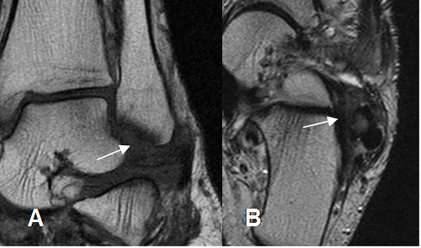

La sinovitis crónica secundaria a la inestabilidad, produce una masa de tejidos blandos, que ocupa el receso anterolateral. (1). Se identifica en la RM, como una imagen irregular hipointensa en T1 y T2, que oblitera el receso. (17). (Fig 92).

Fig 92. Pinzamiento anterolateral.

A: RM coronal en T1. Alteración en la señal y morfología de los componentes del LCL.

B: RM axial en T2. Grupo ligamentario lateral engrosado e hipointenso por fibrosis crónica.